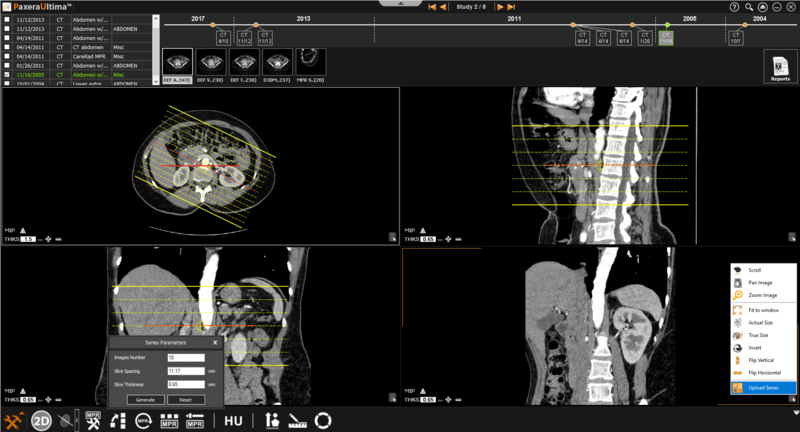

» Generate series - generate a new series from the selected MPR mode.

» MIP - calculates the major intensity of a pixel/region of the selected images